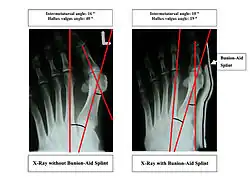

X-ray showing measurements of HV and IM angles of hallux valgus.

Bunions can be diagnosed and analyzed with a simple x-ray, which should be taken with the weight on the foot.[10] The hallux valgus angle (HVA) is the angle between the long axes of the proximal phalanx and the first metatarsal bone of the big toe. It is considered abnormal if greater than 15–18°.[11] The following HV angles can also be used to grade the severity of hallux valgus:[12]

• Mild: 15–20°

• Moderate: 21–39°

• Severe: ≥ 40°

The intermetatarsal angle (IMA) is the angle between the longitudinal axes of the first and second metatarsal bones, and is normally less than 9°.[11] The IM angle can also grade the severity of hallux valgus as:[12]

• Mild: 9–11°

• Moderate: 12–17°

• Severe: ≥ 18°